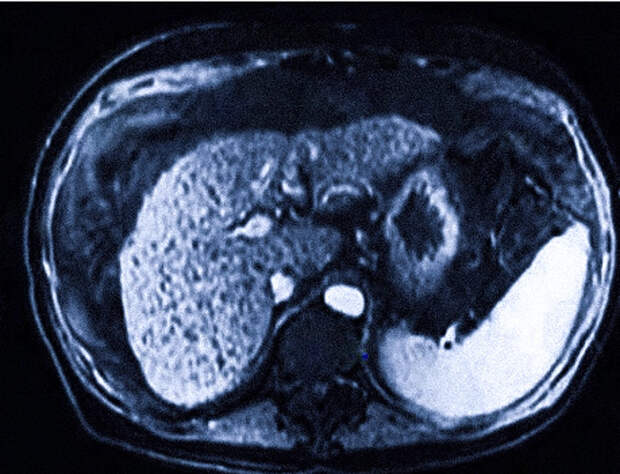

Магнитно-резонансная томография (МРТ) является высокоинформативным неинвазивным диагностическим методом визуализации внутренних органов и тканей организма человека. В частности, МРТ позволяет детально исследовать структуру и функциональное состояние печени, выявляя патологические изменения на ранних стадиях развития заболеваний.

Показаниями к проведению МРТ печени являются подозрения на наличие опухолей, кист, воспалительных процессов или повреждений органа вследствие травм. Процедура может проводиться как с контрастированием специальными препаратами, усиливающими четкость изображения, так и без него.